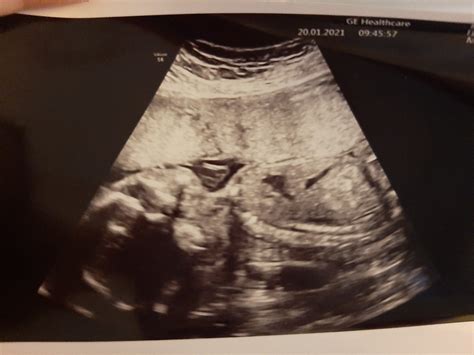

Medzi 19. a 22. týždňom tehotenstva vás čaká druhý veľký ultrazvuk, tzv. morfologický ultrazvuk. Počas neho lekár detailne vyšetrí anatómiu plodu, vnútorné orgány, placentu a krčok maternice. Je to tiež príležitosť dozvedieť sa pohlavie dieťatka a položiť lekárovi akékoľvek otázky.